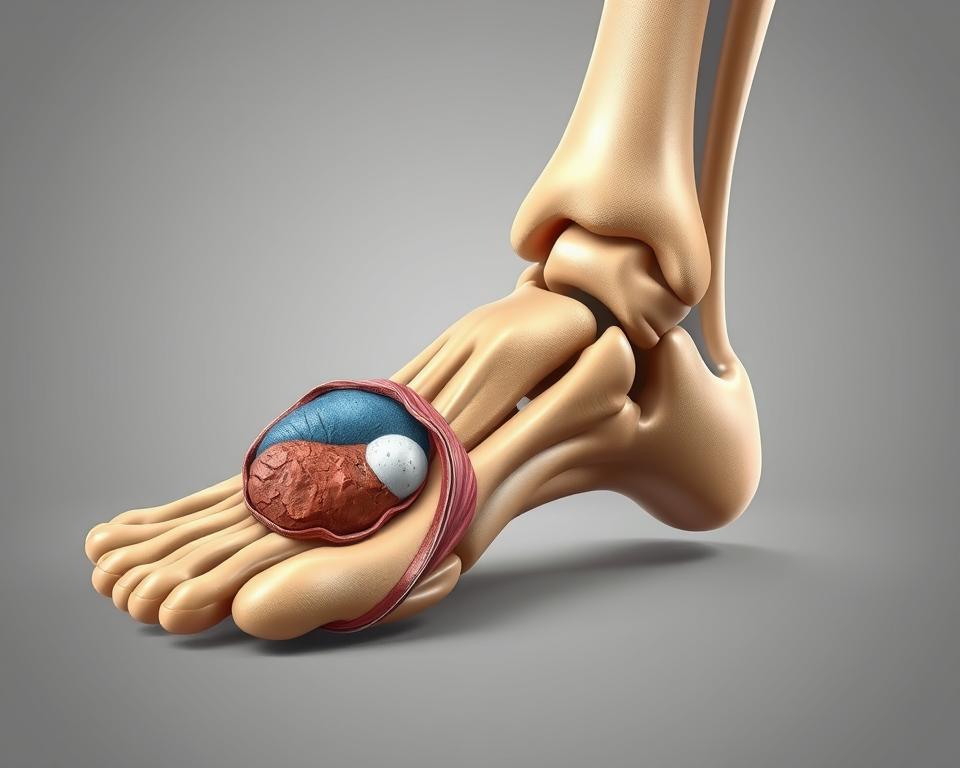

Anatomia torebki stawowej

Zrozumienie budowy tej struktury pomaga lepiej zorientować się w mechanizmach urazów. Torebka stawowa przypomina inteligentnie zaprojektowaną osłonę – łączy elastyczność z wytrzymałością, by sprostać codziennym wyzwaniom.

Budowa: błona maziowa i warstwa włóknista

Wewnętrzna część składa się z delikatnej błony maziowej. Ta żywa fabryka produkuje lepką maź, która działa jak naturalny smar – zmniejsza tarcie podczas ruchu i dostarcza składniki odżywcze do chrząstki.

Zewnętrzna warstwa to gęsta sieć włókien kolagenowych. Układają się one w specyficzne wzory, które decydują o stabilności stawu. W kolanie tworzą mocne pasma, w palcach – bardziej elastyczną siatkę.

Funkcje ochronne i stabilizujące w stawie

Błona maziowa pełni podwójną rolę. Jej gęsta sieć naczyń krwionośnych działa jak filtr – kontroluje przepływ substancji między krwią a płynem stawowym. Jednocześnie produkuje białka chroniące przed infekcjami.

Warstwa włóknista przypomina inteligentny gorset. W spoczynku utrzymuje luźną strukturę, pozwalając na swobodny ruch. Przy nagłym skręceniu natychmiast napina się, blokując niebezpieczne przemieszczenia kości.

Różnice w grubości poszczególnych części tłumaczą, dlaczego kostka goi się inaczej niż nadgarstek. Im większe obciążenia musi znosić staw, tym gęstsze i mniej rozciągliwe są jego warstwy ochronne.